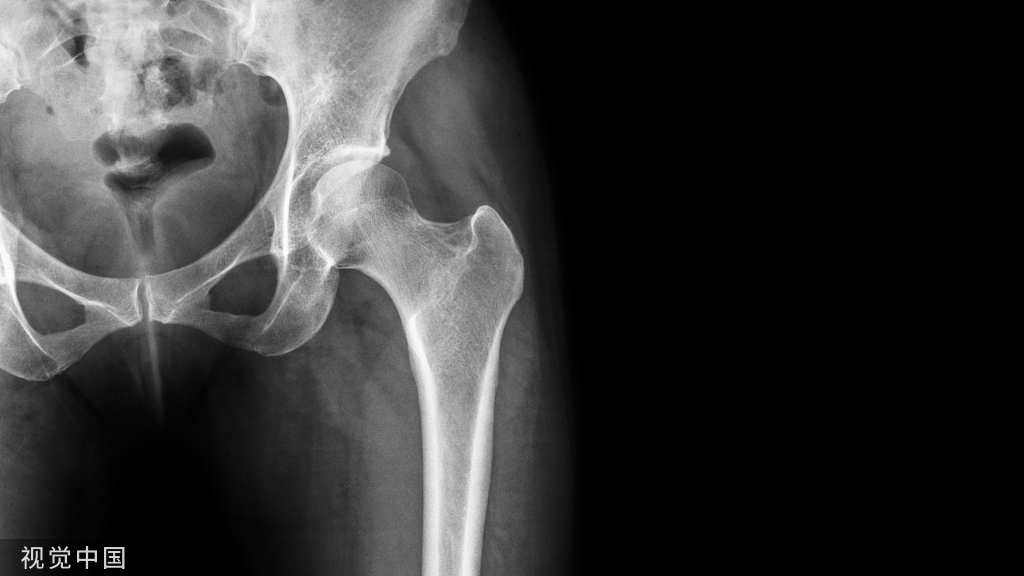

全髋关节置换术中假体的安装角度是影响其术后效果的关键因素之一,合适的假体角度能够使髋关节有良好的活动度,满足术后日常活动的需要

全髋关节置换术中假体的安装角度是影响其术后效果的关键因素之一,合适的假体角度能够使髋关节有良好的活动度,满足术后日常活动的需要,假体角度不良往往与术后脱位、活动受限有关。髋臼前倾角和股骨颈前倾角之和的概念最初由McKibbin在1970年提出,被称为“不稳定指数”。